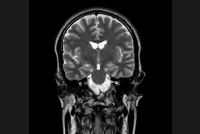

Comprehensive Brain imaging at 3.0T